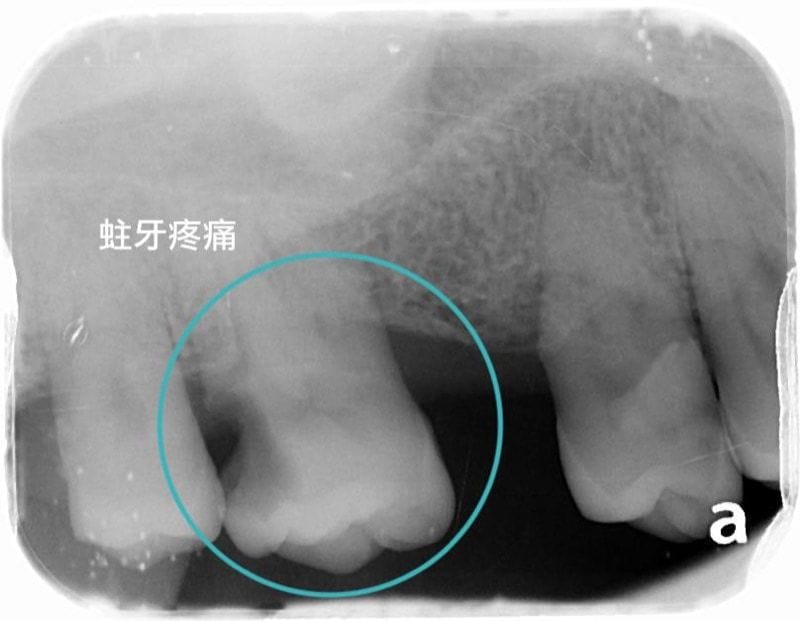

患者陳小姐是一位五十多歲的女性,她因右上的臼齒蛀牙疼痛到診所就診。一般牙科的醫師幫她做根管治療並且預計用牙套修復。因為隔壁顆是缺牙,因此一般牙科醫師便將患者轉診到我這裡評估植牙。

圖示:患者右上臼齒蛀牙的X光片

我們發現到患者的牙周與齒槽骨流失超過50%,缺牙一共有三顆。診斷是全口嚴重牙周病(第三期)。